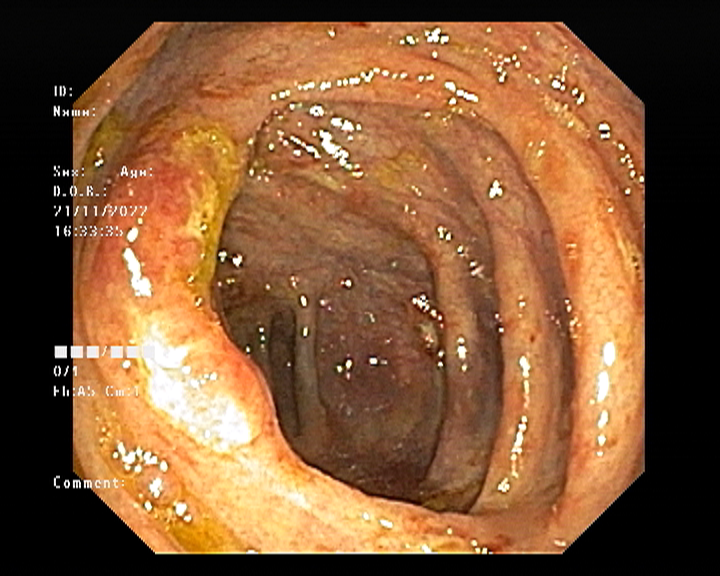

Endoscopy and colonoscopy are safe and accurate procedures used to directly examine the digestive tract and detect the root cause of chronic acidity, GERD, abdominal pain, bleeding, and bowel irregularities. These minimally invasive tests help identify ulcers, inflammation, infections, polyps, strictures, and early cancerous changes.

At Sapphire Gastroenterology Center, modern endoscopic equipment ensures precise diagnosis and, when required, therapeutic intervention during the same procedure. Based on findings, targeted treatment plans are created, including medication, diet guidance, and preventive strategies. Early diagnosis through endoscopy and colonoscopy plays a crucial role in preventing serious complications and improving long-term digestive health.